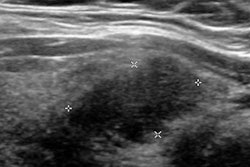

Guide for ob/gyn US

Finally, visit our Ultrasound Community for news on a new set of guidelines issued by the American Institute of Ultrasound in Medicine designed to improve the use of ultrasound in obstetrics and gynecology. Read all about it by clicking here, or go to ultrasound.auntminnie.com.